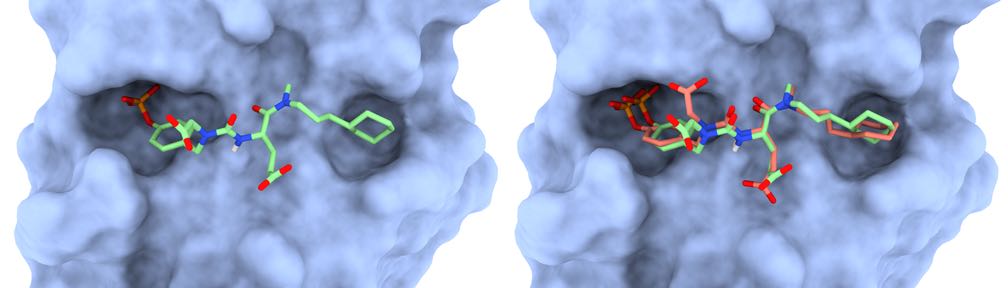

- Structure-based identification of SARS-derived peptides with potential to induce broad protective immunity

- Structure-based Selection of Tumor-antigens for T-cell Based Immunotherapy

- Structural modeling of peptide-HLA complexes presenting a melanoma-associated antigen for cross-reactivity assessment